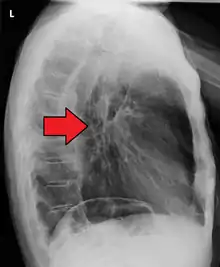

Additional testing is needed to assess how much the cancer has spread (see § Staging, below). Computed tomography (CT) of the chest, abdomen and pelvis can evaluate whether the cancer has spread to adjacent tissues or distant organs (especially liver and lymph nodes). The sensitivity of a CT scan is limited by its ability to detect masses (e.g. enlarged lymph nodes or involved organs) generally larger than 1 cm.[43][44] Positron emission tomography is also used to estimate the extent of the disease and is regarded as more precise than CT alone.[45] PET/MR as a novel modality has shown promising results in preoperative staging with fair feasibility and good correlation in comparison to PET/CT. It can enhance tissue differentiation with lowering the radiation dose to the patient.[46] Esophageal endoscopic ultrasound can provide staging information regarding the level of tumor invasion, and possible spread to regional lymph nodes.

Contrast CT scan showing an esophageal tumor (axial view)